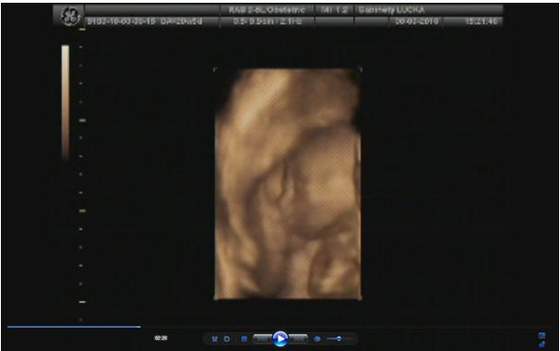

Witam, ja też po wizycie, wszystko u nas ok, maluch ma już prawie 1 kg tzn 970g- olbrzym niesamowity!